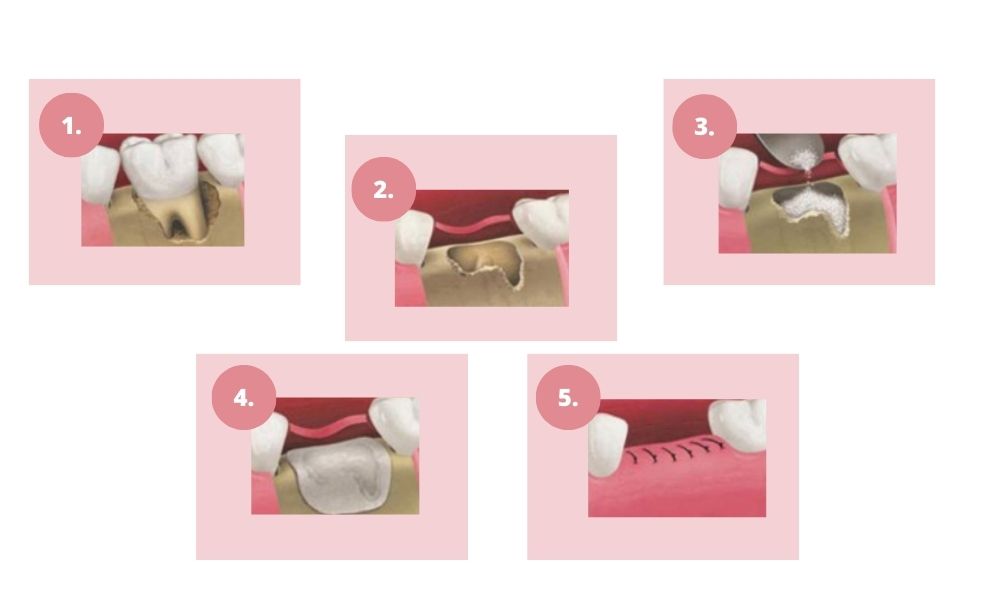

A beavatkozás menete:

- Helyi érzéstelenítés után lebenyt képez, és egy csontablakot képez, amin keresztül elérhető az arcüreg nyálkahártyája

- Megemeli az arcüreg nyálkahártyáját, majd az így létrejött térbe csontpótló anyagot helyez. Ezzel erősíti meg a csontszerkezetet vagy növeli a csontállományt, lehetővé téve az implantátumok biztonságos és sikeres beültetését.

- A csontablakot a csontpótló tetejére visszahelyezi, vagy membránt használ és titán szegecsekkel rögzíti a csontozathoz, melynek feladata, hogy a csontpótló anyagot rögzítse a regenerálódási időszak során.

- Varratokkal zárja a műtéti területet.

A gyógyulási időszak alatt a csontpótló anyag fokozatosan integrálódik a meglévő csontszövetbe. Amennyiben a beavatkozás nem az implantátum behelyezésével egyidőben történik, a csont megerősödését követően nyílik lehetőség az implantátumok beültetésére.